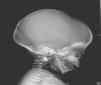

Inicialmente, se realiza una radiografía craneal donde se observan esclerosis y engrosamiento de la base del cráneo (fig. 1). Ante estos hallazgos, ampliamos el estudio radiológico, evidenciándose un aumento difuso de la densidad ósea (fenómeno hueso dentro de hueso), llamativo a nivel de los cuerpos vertebrales (fig. 2), esclerosis de costillas y huesos de la pelvis, y metáfisis en «maza» de huesos largos, donde no se reconoce cavidad medular.

Ante estas imágenes radiológicas compatibles con displasia ósea, se procede a realizar las siguientes pruebas: análisis sanguíneo (Hb: 8,0 g/dl; hematocrito: 24,8%; leucocitos 31.600/μl [neutrófilos 33%, linfocitos 47%, monocitos 10%, eosinófilos 2%, basófilos 0%]; eritroblastos 5%; células inmaduras 1%; plaquetas 73.000/μl; calcio 8,37 mg/dl; fósforo 2,92 mg/dl; fosfatasa alcalina: 950 U/l; PTH 220 pg/ml), ecografía abdominal (hepatoesplenomegalia); ecografía cerebral (alteración de la ecogenicidad de sustancia blanca subcortical); potenciales evocados visuales (ausentes); potenciales auditivos (hipoacusia bilateral de 50 dB); RM cerebral (significativo engrosamiento de la calota en base del cráneo), y TC craneal (órbitas pequeñas por aumento de densidad ósea, proptosis ocular bilateral, agujeros ópticos permeables, cajas timpánicas bien configuradas).